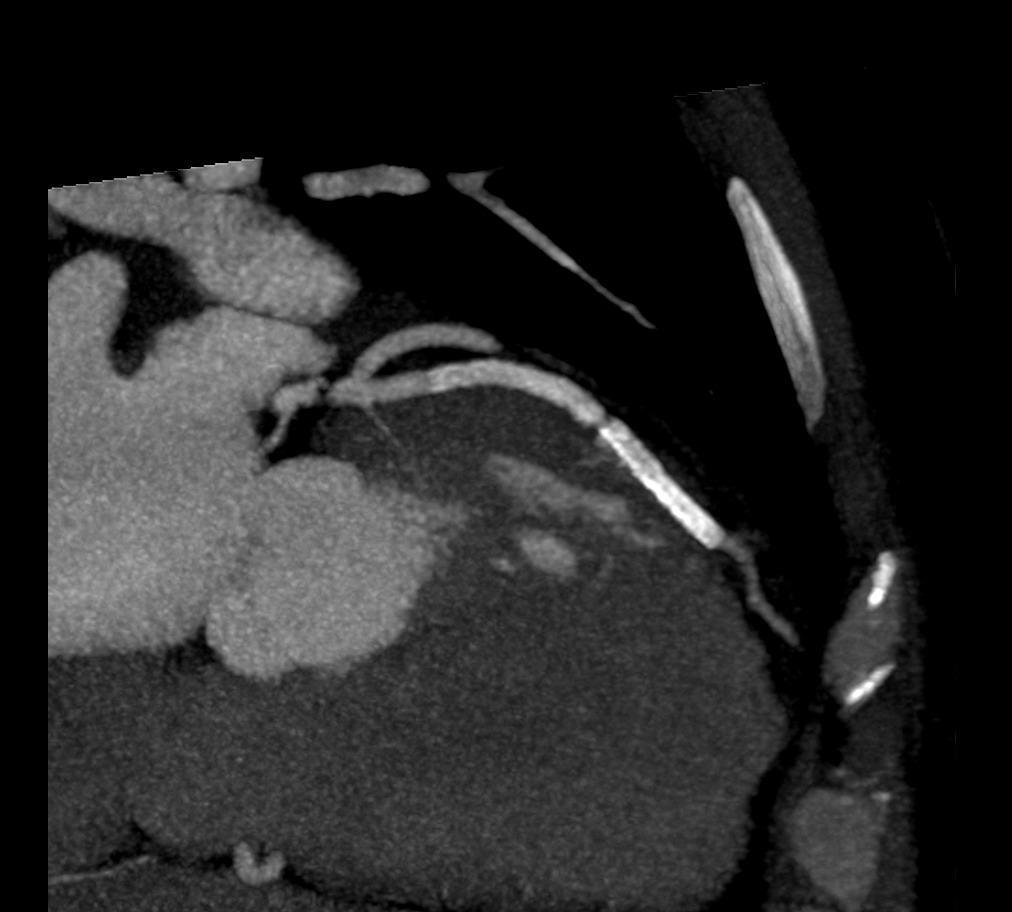

以下是引用zjzjr在2007-6-22 22:20:00的发言:[br]右冠状动脉多发狭窄,左冠状动脉支架断裂或两个支架连接欠佳。

以下是引用尚峰在2007-6-22 22:47:00的发言:[br]支架是不可能断裂的,这个病人左冠前降支病变太长,下了两个支架,但下两个支架的一个原则是两根支架必须重叠3-5mm,不知什么原因此患者两根支架没有重叠上,现在很麻烦了,要么再下一根支架,要么搭桥。